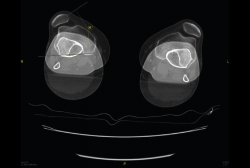

5.1. TA-GT (tuberosidad tibial anterior-garganta de la tróclea)

En pacientes sintomáticos con inestabilidad rotuliana, la TAC es útil para medir la TA-GT(10). La distancia TA-TG es una medida radiológica propuesta por Goutallier y Bernageau que sirve para cuantificar el ángulo Q. Consiste en medir la distancia en milímetros de la tuberosidad tibial anterior a la garganta de la tróclea proyectadas sobre una línea que pasa por los bordes posteriores de ambos cóndilos femorales, superponiendo 2 cortes axiales de TAC. Es una medida fiable y reproducible pero poco precisa, con un margen de error de más de 4 mm. La distancia TA-GT es mayor de 20 mm en el 56% de las inestabilidades rotulianas y tan solo en el 3% de la población sana(11) (Figura 28).

5.2. Balance rotuliano

Mide la inclinación de la rótula en relación con el borde posterior de los cóndilos femorales (Figura 29).

Figura 28. Corte axial de tomografía axial computarizada con superposición de imágenes con rótula y parte posterior de cóndilos y tuberosidad tibial anterior, que nos permite medir la distancia TA-GT, en condiciones normales hasta 2 cm.

Figura 29. Corte axial de tomografía axial computarizada con superposición de imágenes con rótula y parte posterior de cóndilos y tuberosidad tibial anterior, que nos permite medir el tilt o balance rotuliano, en condiciones normales hasta 20°.